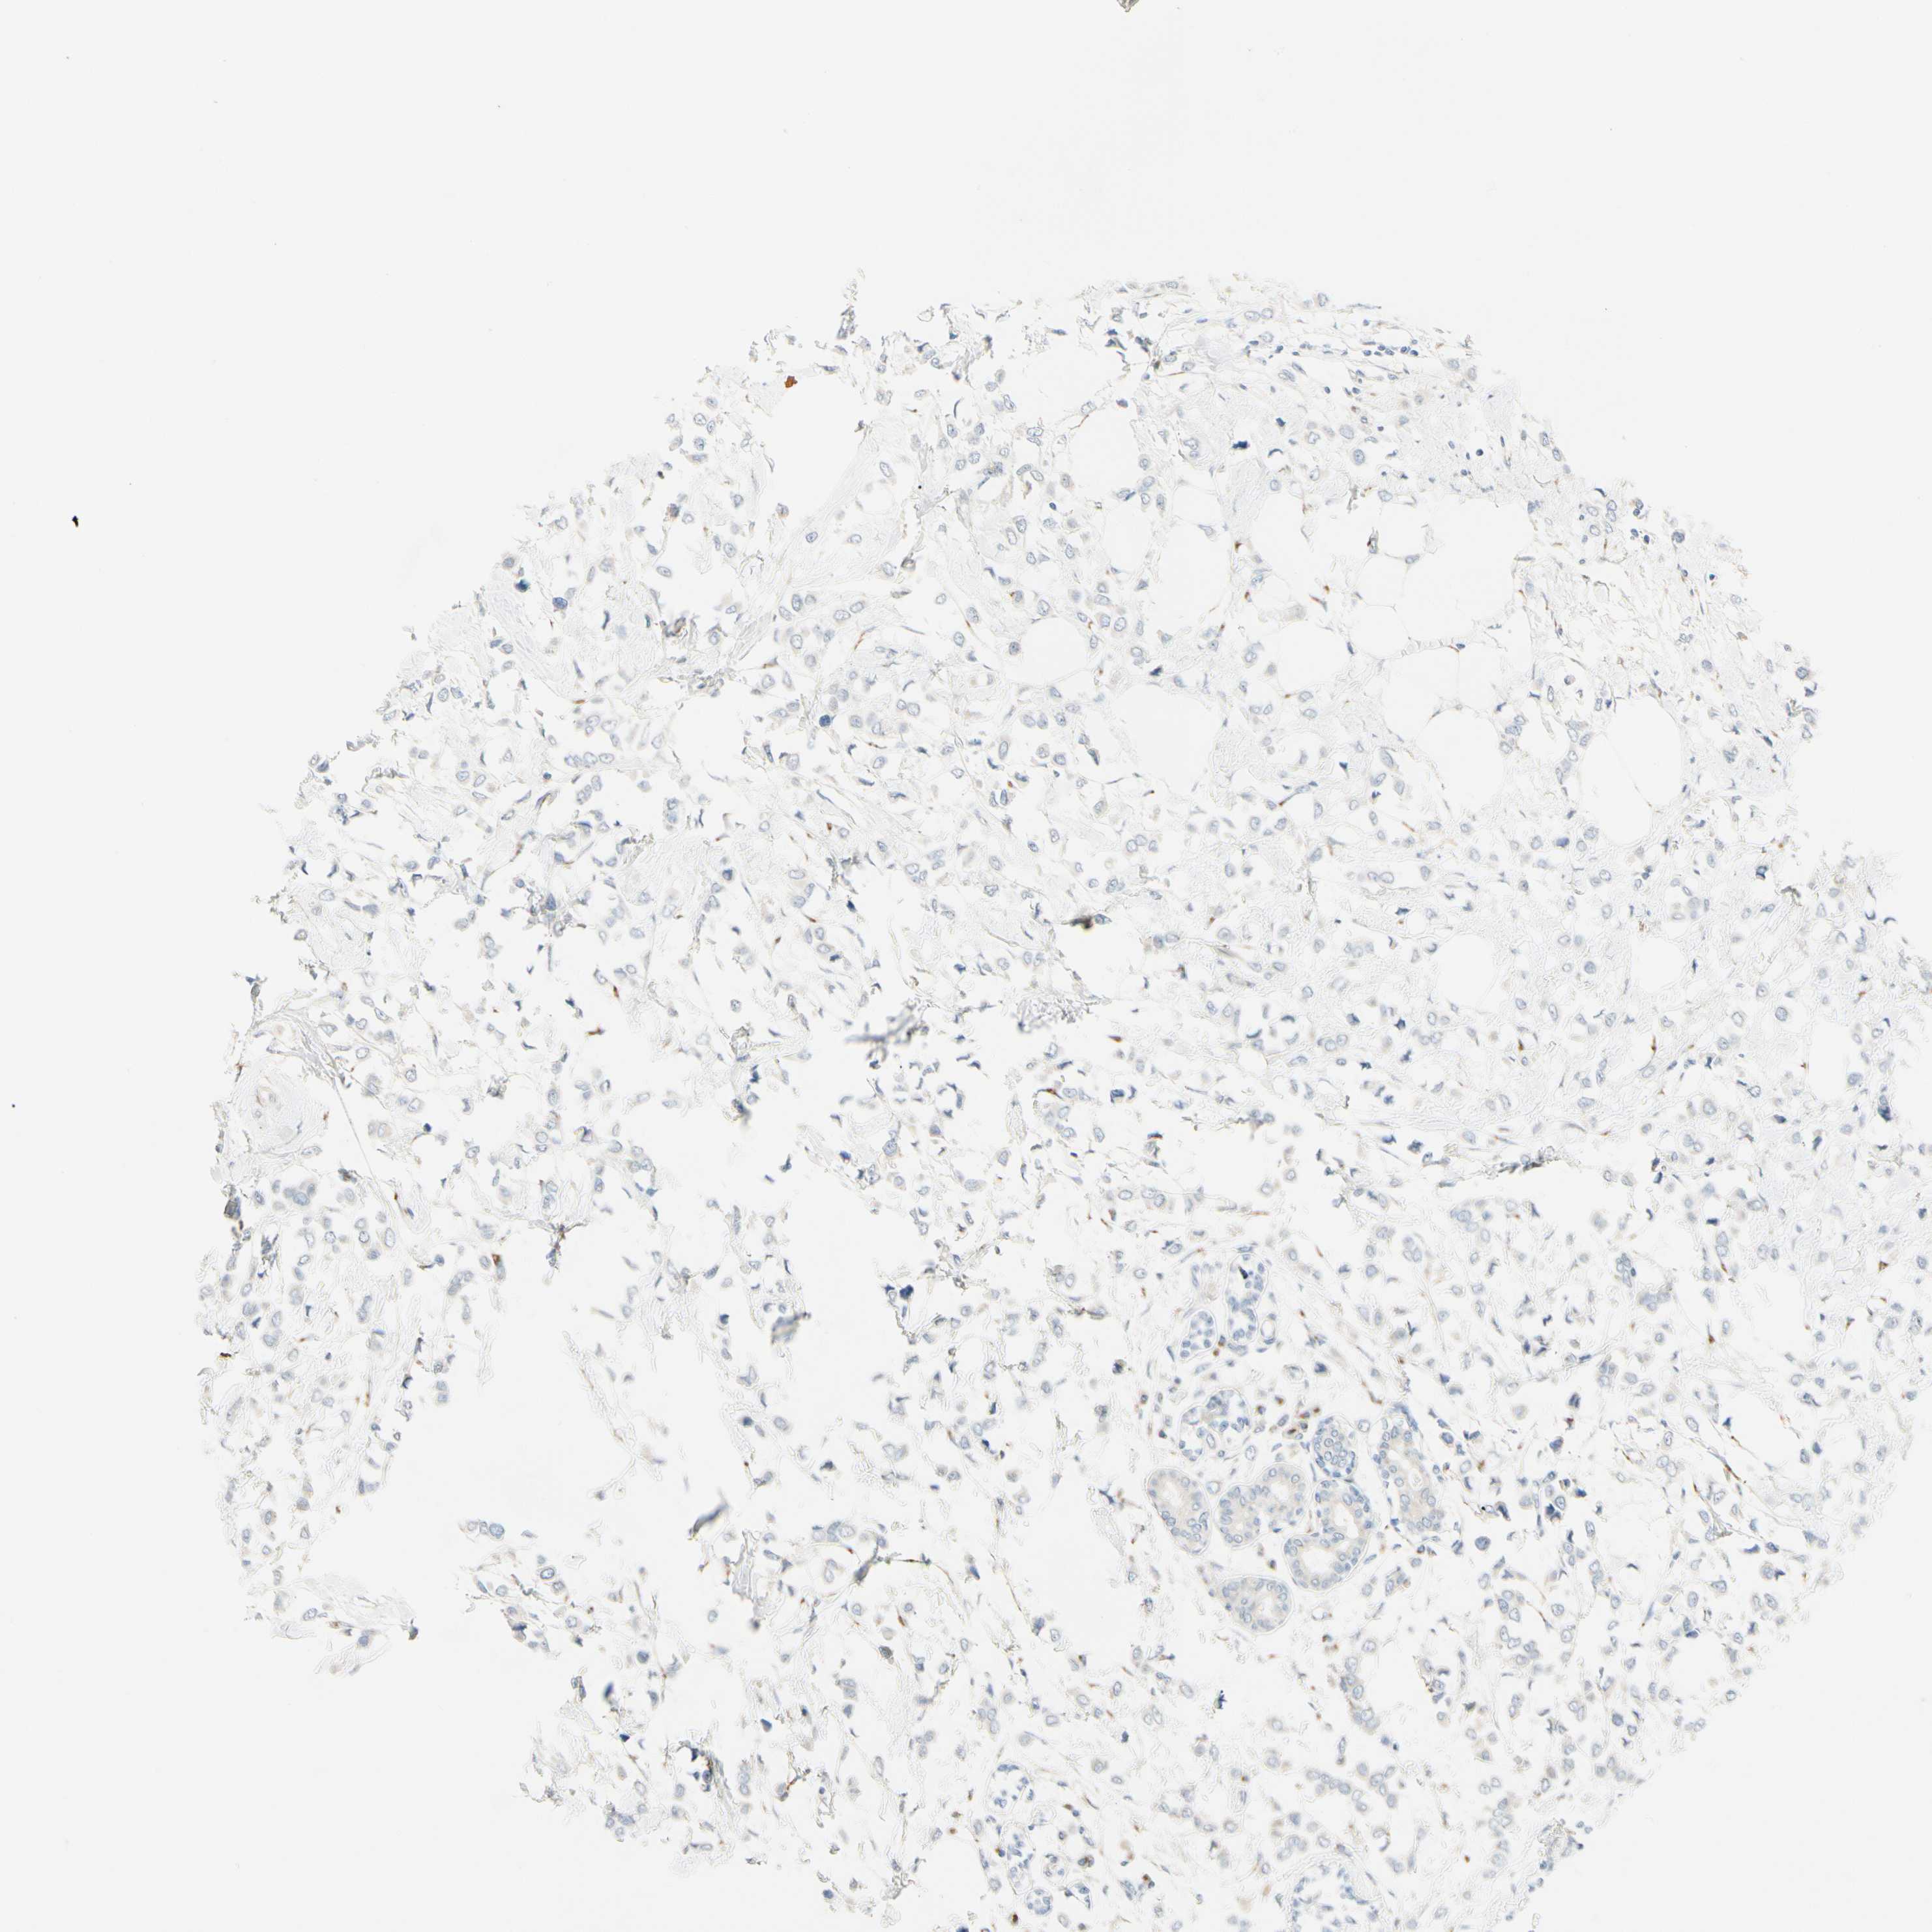

CANCER BREAST CANCER Show tissue menu

BRCA TCGA BRCA VALIDATION PROTEIN EXPRESSION